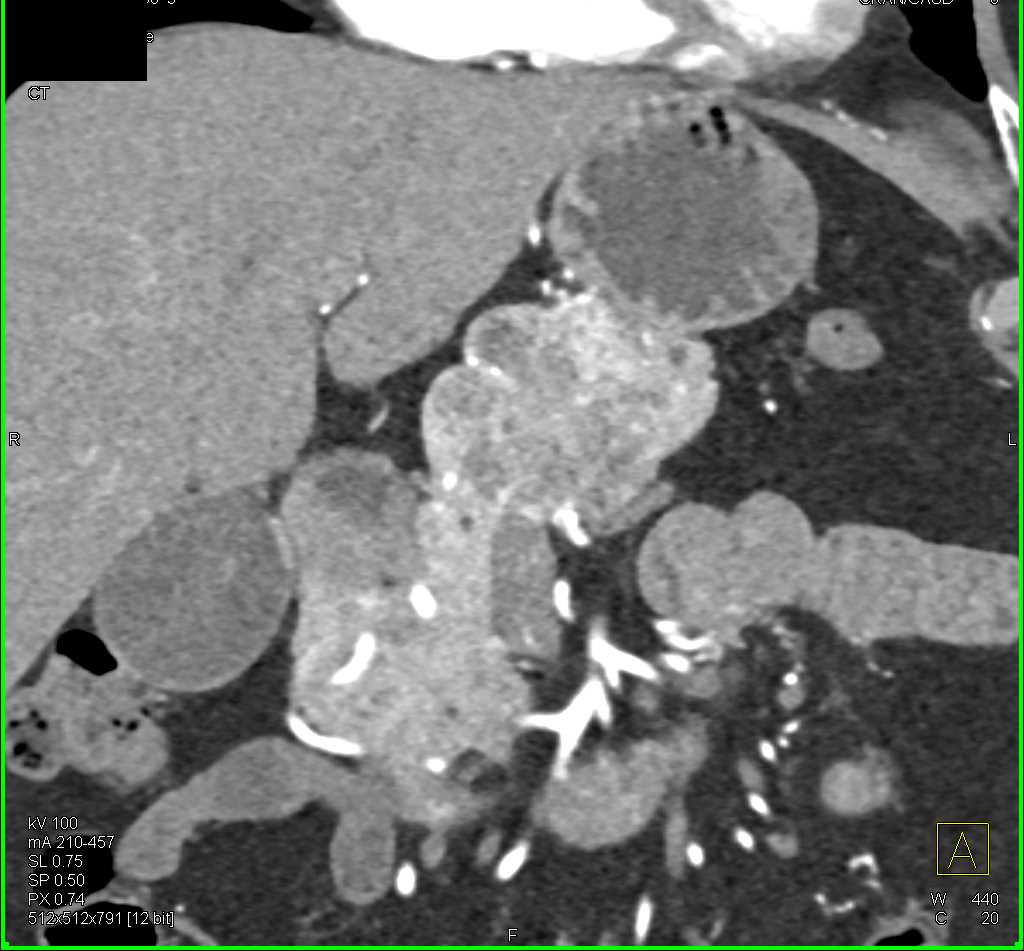

Multiple Intraductal Papillary Mucinous Neoplasms (IPMNs)